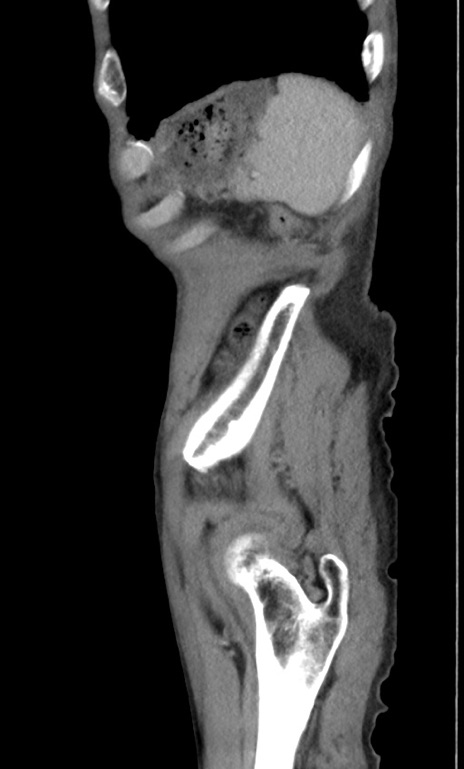

症例3(矢状断像)

【症例】 70歳代男性

【主訴】右鼠径部腫瘤、疼痛

【現病歴】本日朝より上記主訴あり、受診。

【既往歴】膀胱癌にて膀胱全摘、両側尿管皮膚瘻

【データ】WBC 5600、CRP 0.56